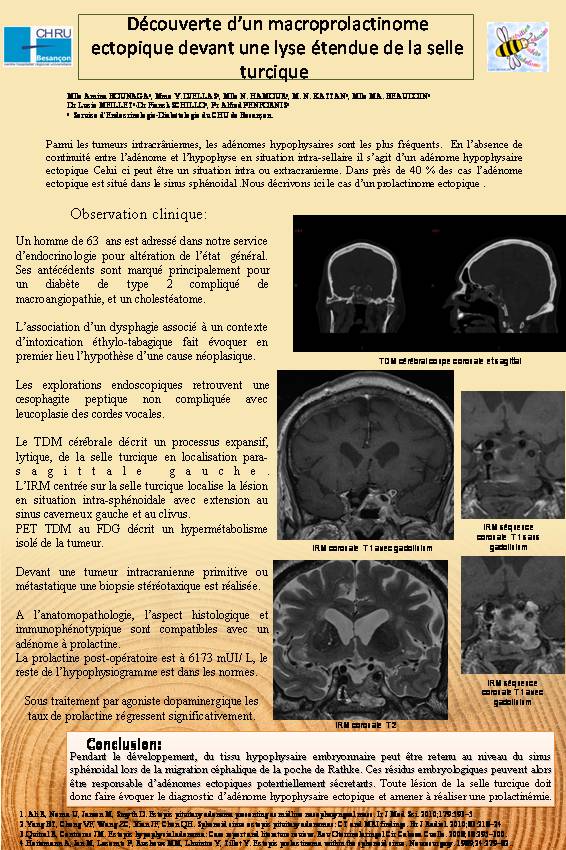

Au terme du bilan initial on diagnostique une leucoplasie des cordes vocales et une œsophagite peptique. Par ailleurs,  il est décrit au scanner cérébral  un processus expansif, lytique, de la selle turcique en localisation para-sagittale gauche.

L’IRM  cérébrale met en évidence une tumeur intra-sphénoïdale  avec extension au sinus caverneux gauche et au clivus. La lésion est hyperfixante au PET- TDM.